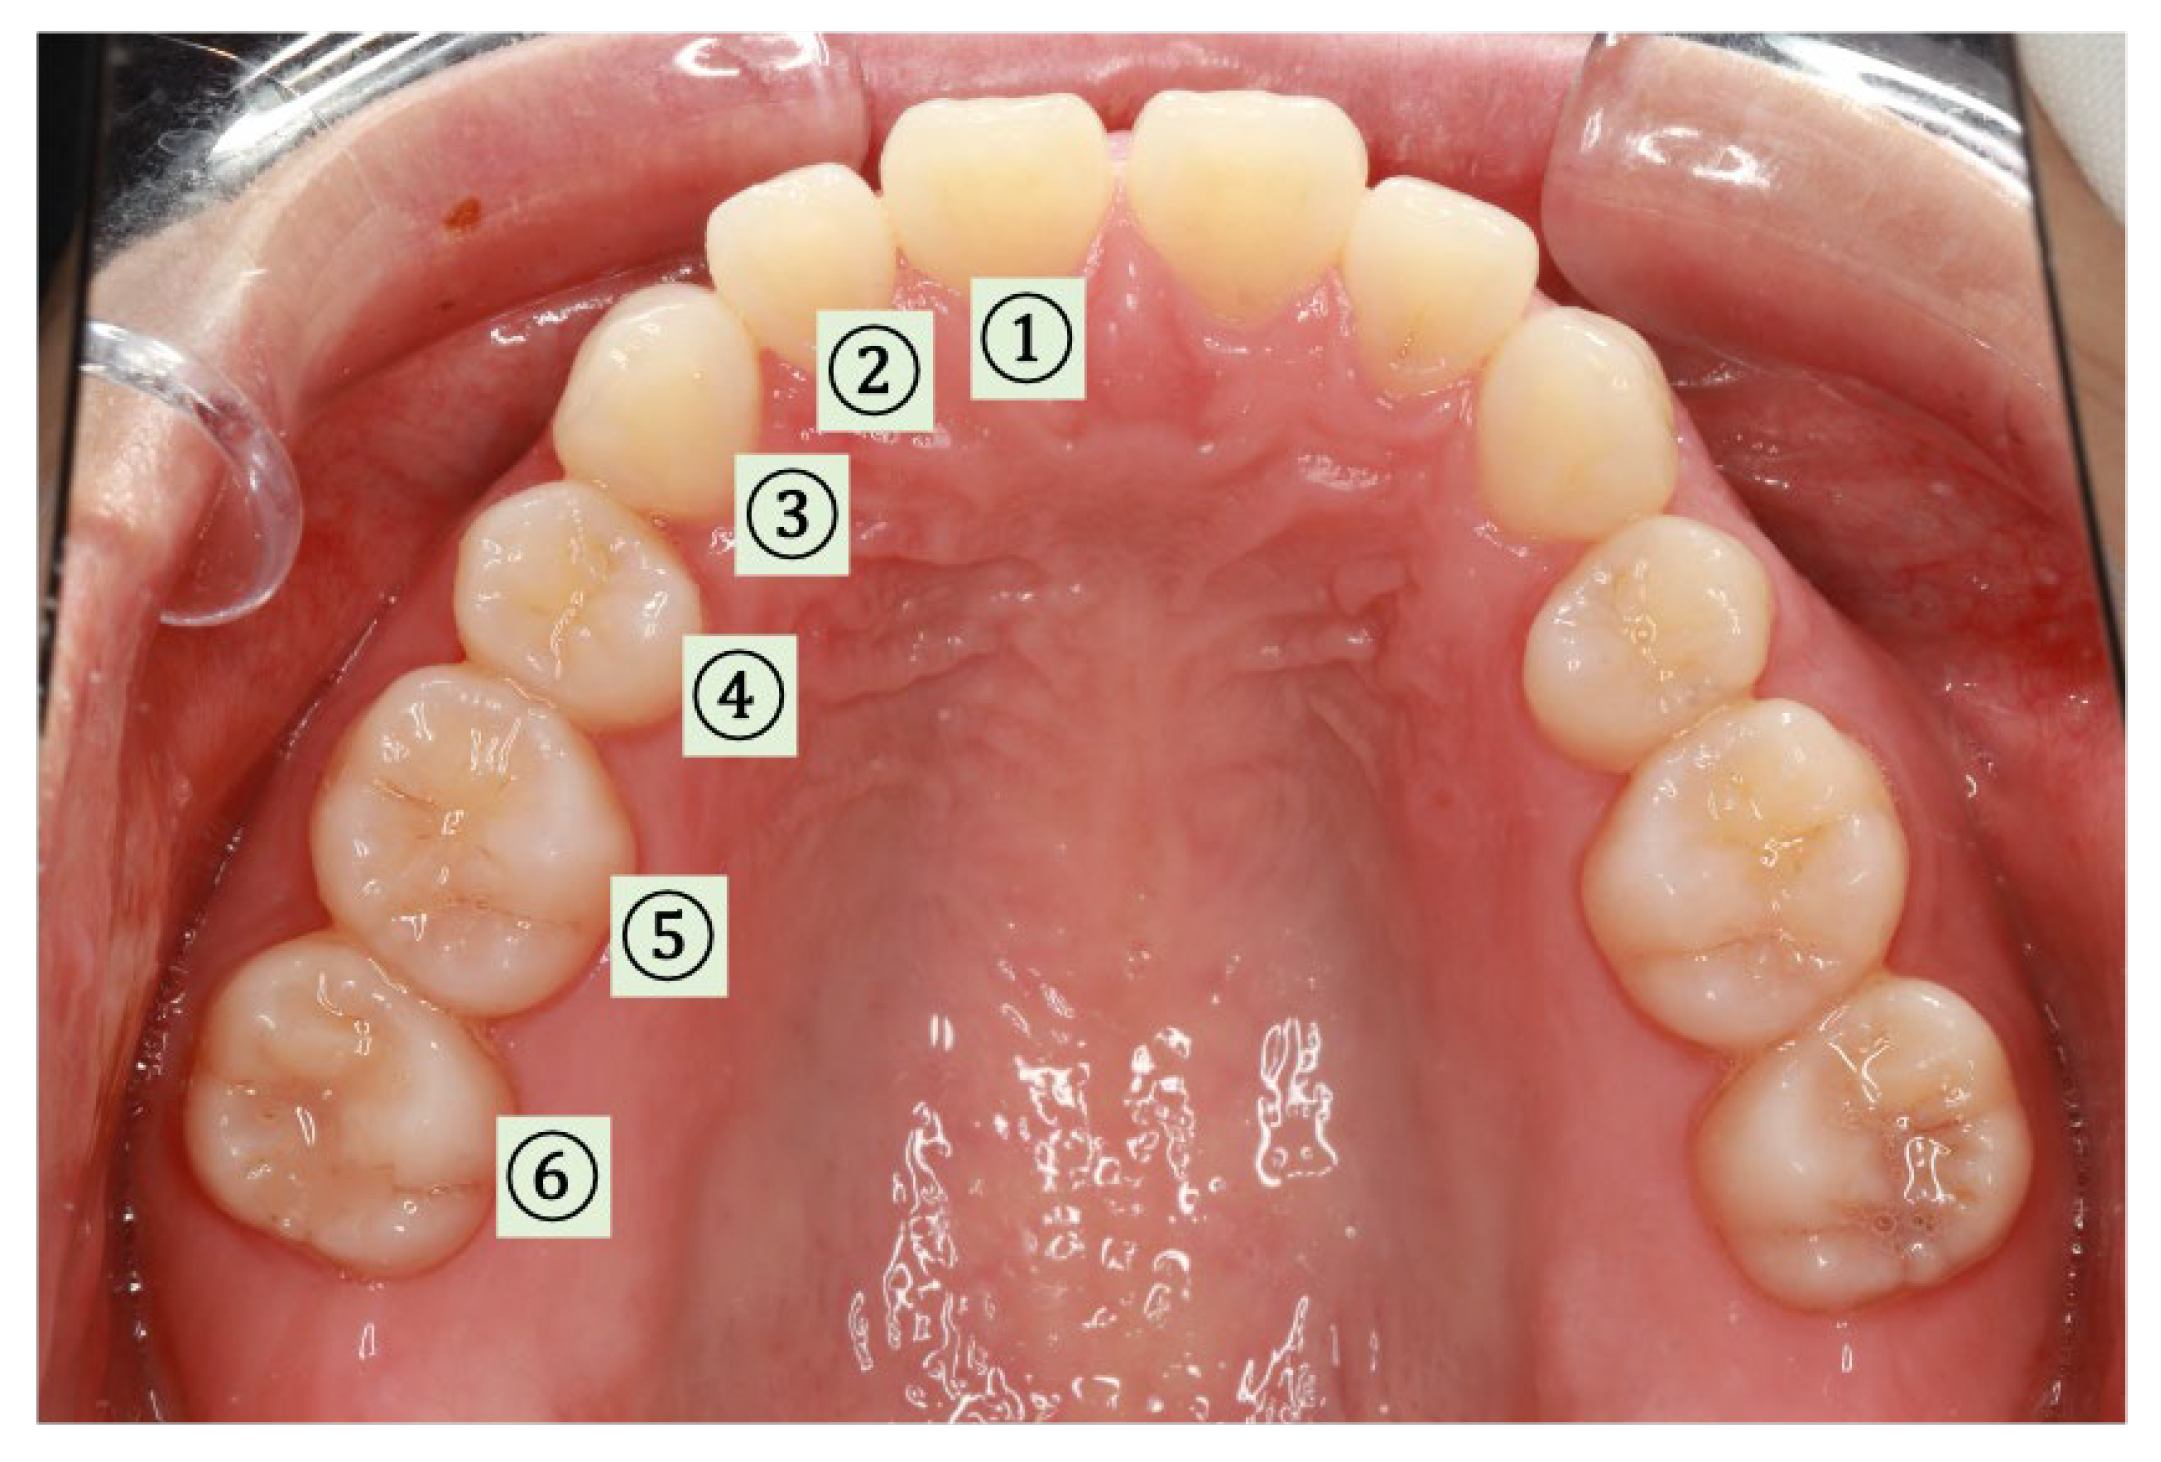

2.3.3. SpO2 and Pressure Measurements at Different Locations (Intraoral)

3.3.1. SpO2 and Pressure (Intraoral)